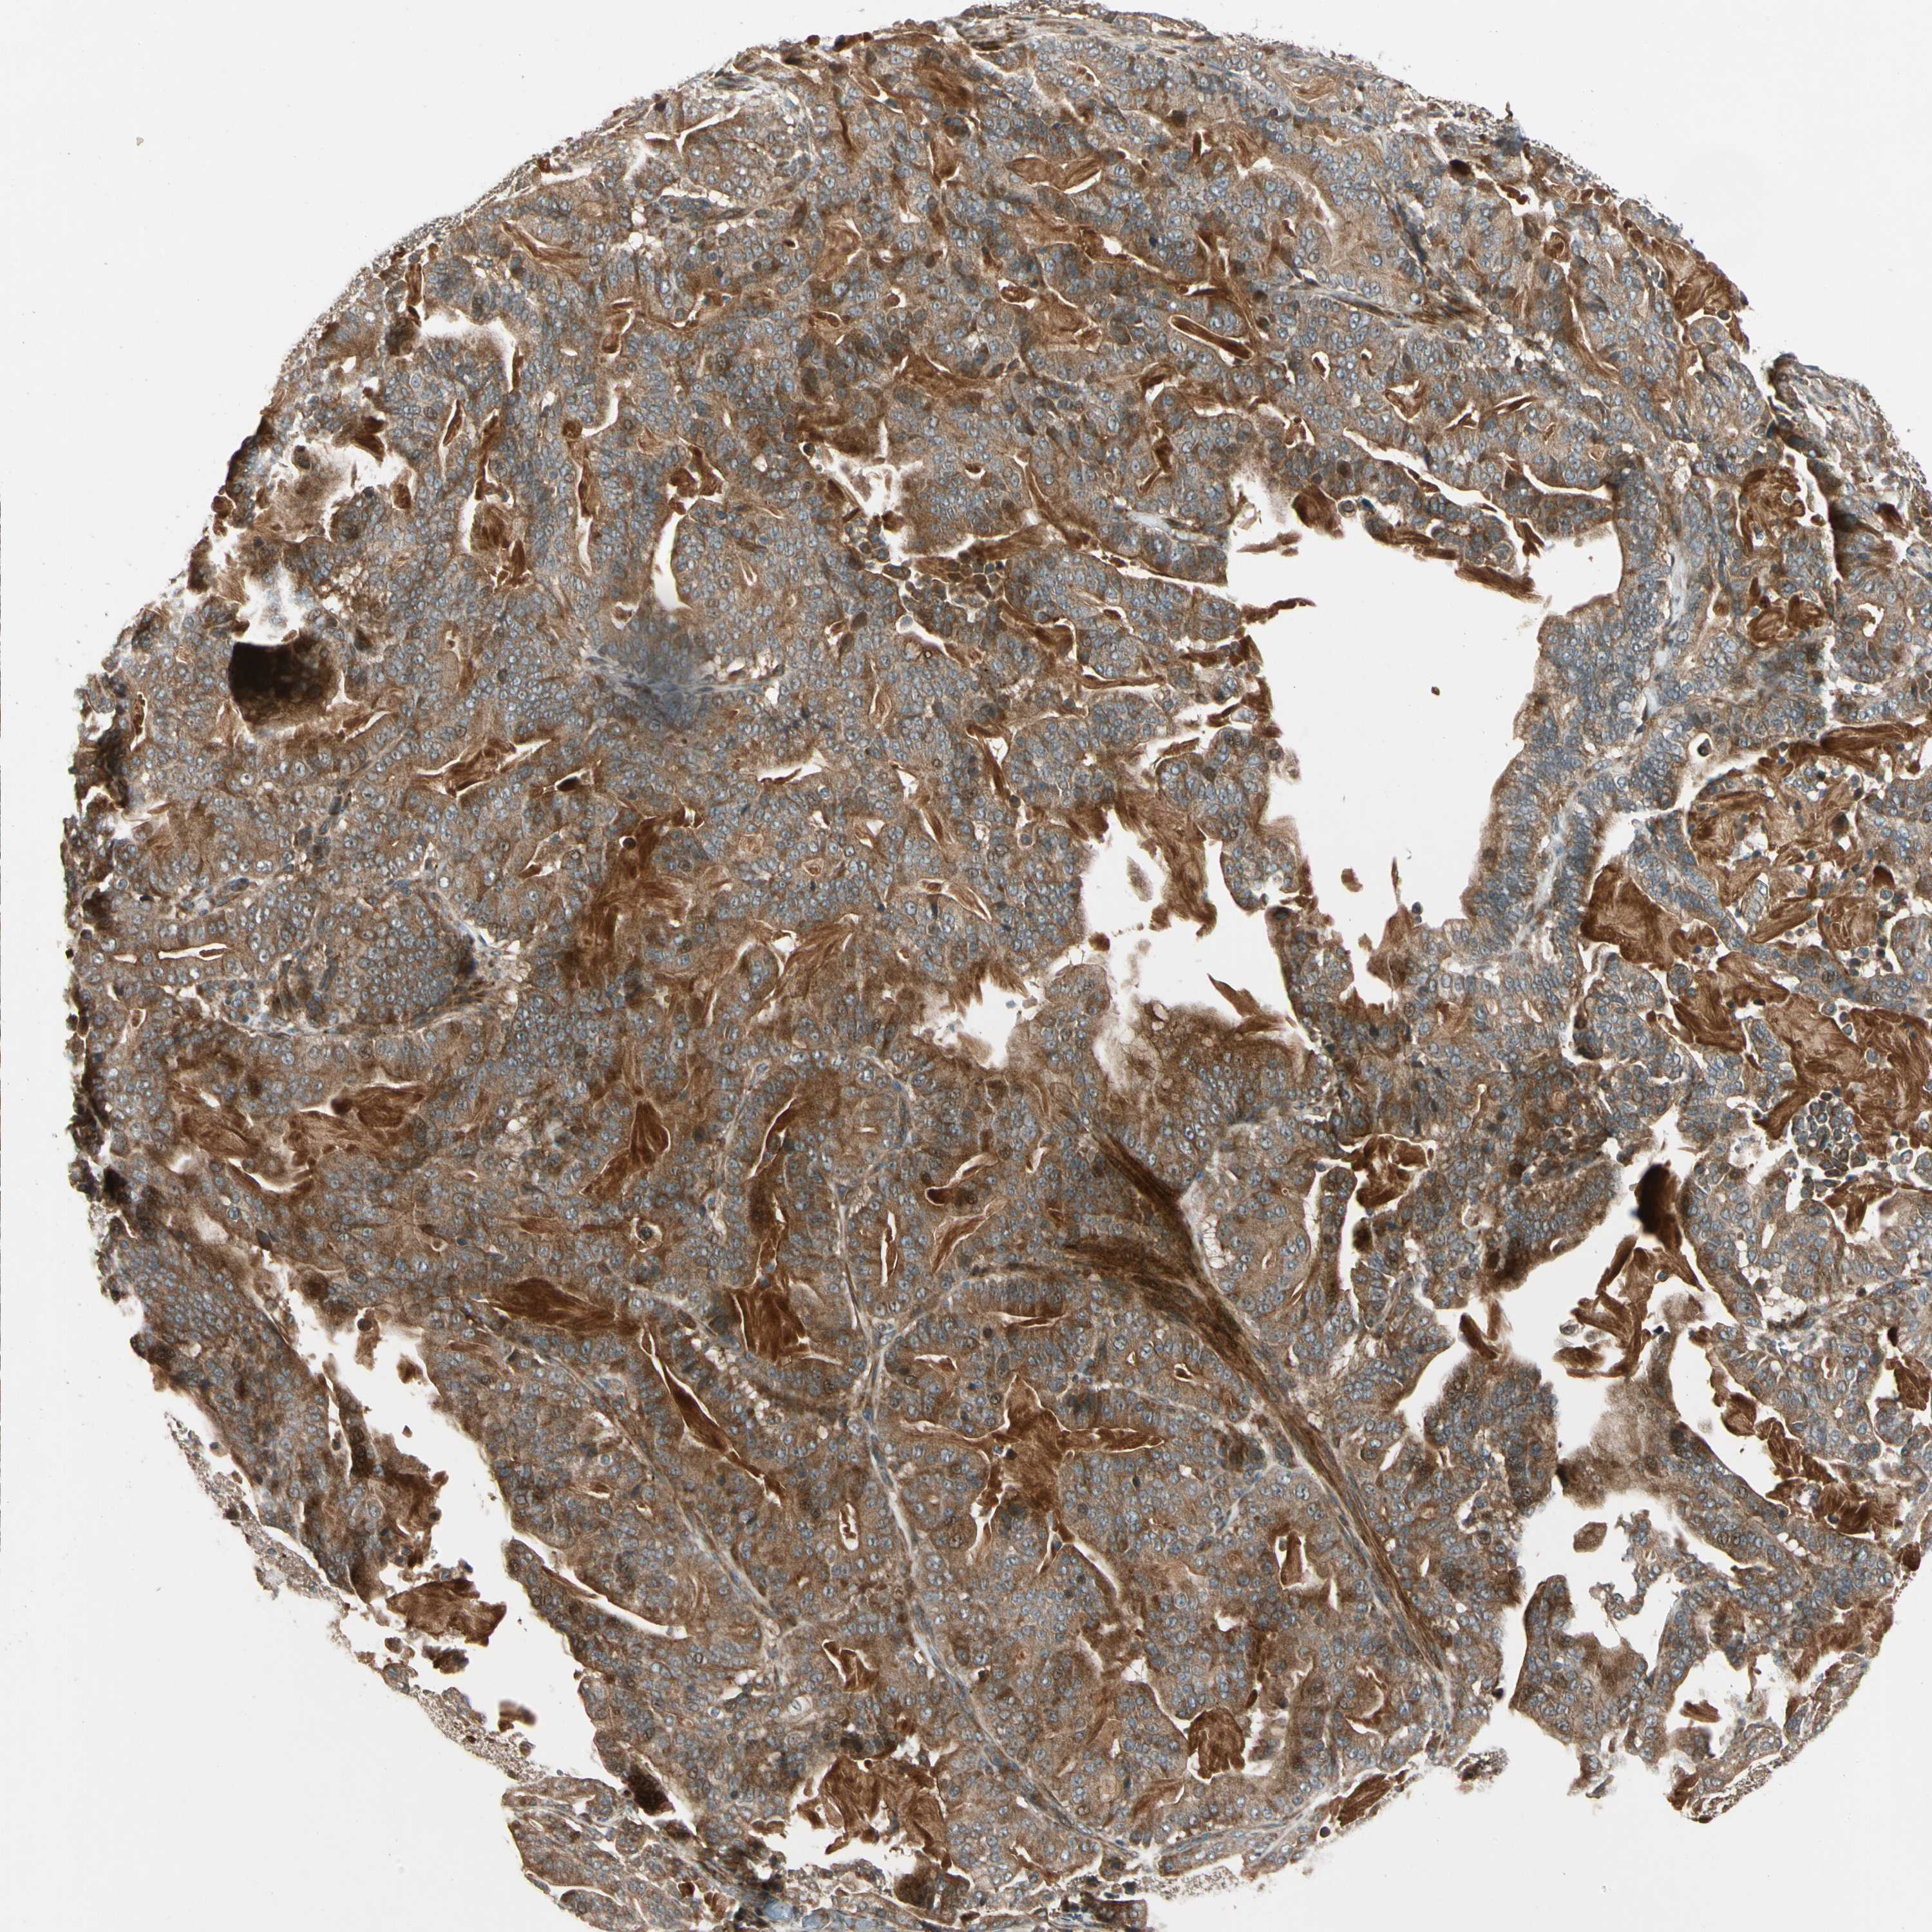

PANCREATIC CANCER - Protein expressioni

A mouse-over function shows sample information and annotation data. Click on an image to view it in a full screen mode. Samples can be filtered based on level of antibody staining by selecting one or several of the following categories: high, medium, low and not detected. The assay and annotation is described here.

Note that samples used for immunohistochemistry by the Human Protein Atlas do not correspond to samples in the TCGA dataset.

Antibody stainingi

Antibody staining in the annotated cell types in the current human tissue is reported as not detected, low, medium, or high, based on conventional immunohistochemistry profiling in selected tissues. This score is based on the combination of the staining intensity and fraction of stained cells.

Each image is clickable and will lead to virtual microscopy that enables deeper exploration of all samples and also displays staining intensity scores, fraction scores and subcellular localization as well as patient and tissue information for each sample.

Antibody HPA007982

Antibody HPA011933

Staining

High

Medium

Low

Not detected

Intensity

Strong

Moderate

Weak

Negative

Quantity

>75%

75%-25%

<25%

None

Location

Nuclear

Cytoplasmic/membranous

Cytoplasmic/membranous,nuclear

Adenocarcinoma, NOS

Adenocarcinoma, metastatic, NOS